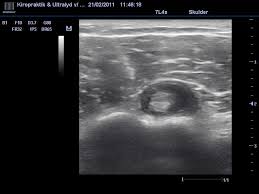

Spa Imaging Org

Spa Imaging Org from www.spa-imaging.org